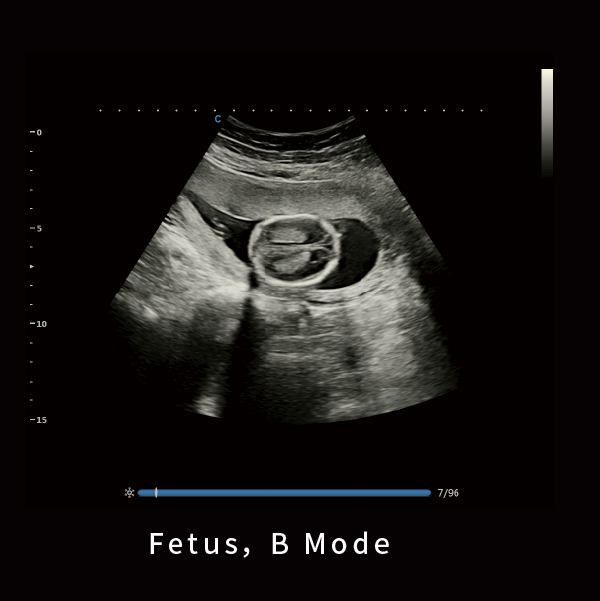

胎儿,B模式